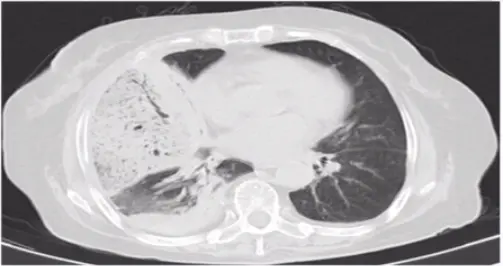

第一题:如下图所示,病变表现为肺实质炎症,贴近脏层胸膜或者叶间裂,有支气管充气征。

第一题答案:肺炎链球菌肺炎,通常也被称为大叶性肺炎。